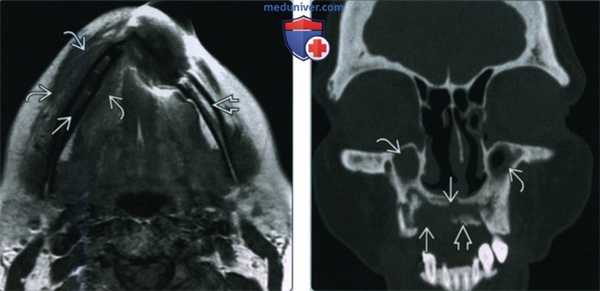

(Слева) При МРТ Т1ВИ в аксиальной проекции у пациентки, находящейся на лечении бисфосфонатами по поводу рака молочной железы, с жалобами на боль в области челюсти, определяется отек нижней челюсти справа с сигналом низкой интенсивности, тогда как слева сигнал в коаном мозге не изменен. Определяется также перифокальное воспаление мягких тканей.

(Справа) Корональная КТ в костном окне, признаки тяжелого остеонекроза и дстарукции верхней челюсти у пациента с множественной миеломой (после внутривенного введения бисфосфонатов). Обратите внимание на костный секвестр. Определяется снижение пневматизации верхнечелюстной пазухи, которое, скорее всего, не связано с остеонекрозом.